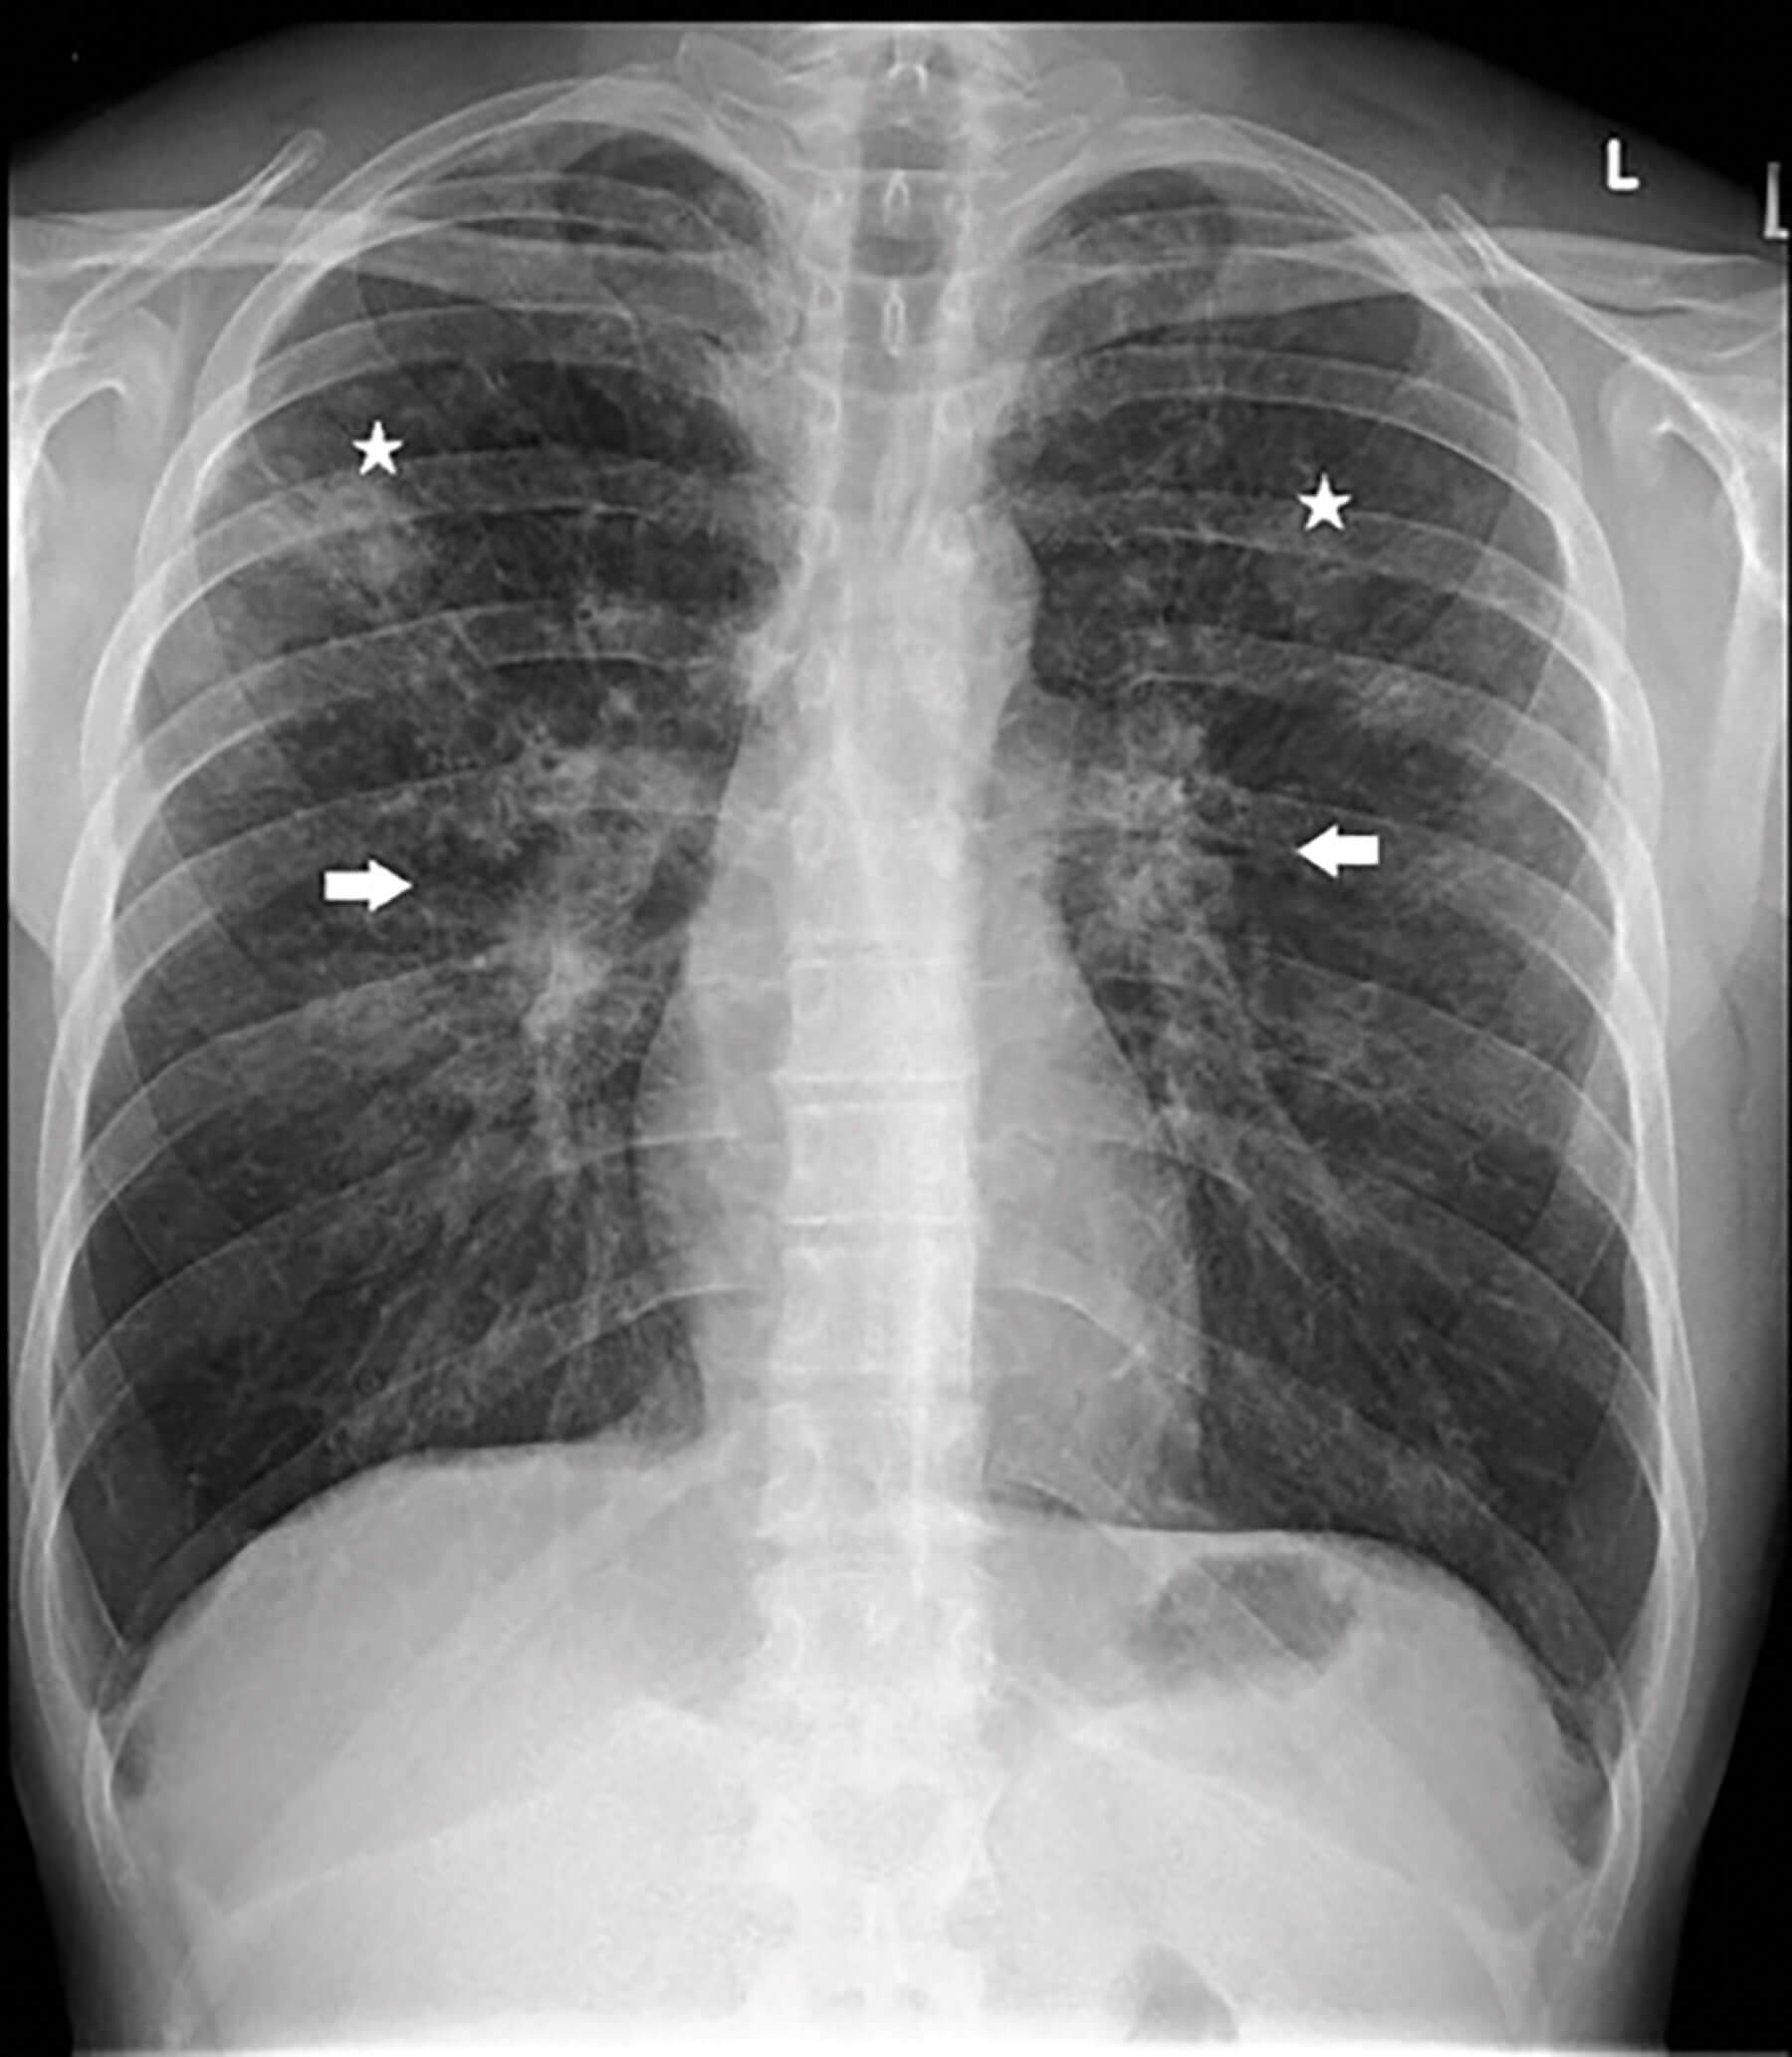

He returned to his scheduled clinic appointment four weeks later with persisting ocular and systemic symptoms. Examination revealed persistent right anterior uveitis with vitritis. A new ciliary body mass was seen temporally through dilated pupil (Figure 1A) and on fundus examination (Figure 1C). Relevant blood tests were obtained as shown in Table 1 and chest X-ray (Figure 2) was performed.

Figure 2: Chest X-ray showing nodular lung infiltrates (white asterisks) and bilateral hilar prominence

(white arrows). Note: Consent obtained from patient to publish case history and images.

Subsequently, he also had chest high resolution computed tomography (HRCT) which revealed widespread nodular pulmonary lesions in the upper lung zones with extensive lymphadenopathy; indicative of pulmonary sarcoidosis.

Chest HRCT evaluates lesions seen on chest radiograph in greater detail and can detect parenchymal and mediastinal abnormalities. It revealed widespread pulmonary nodular lesions with extensive lymphadenopathy in our patient which are typical radiographic features of pulmonary sarcoidosis [5].